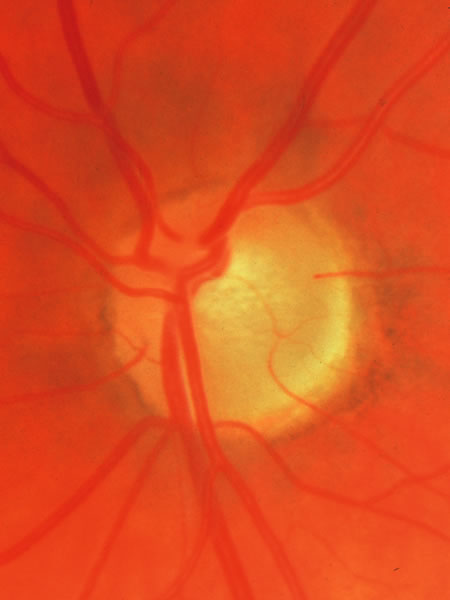

Fig. 33. Swollen disc tissue during an acute attack of angle closure glaucoma.

In acute angle-closure glaucoma (Fig. 33), the optic disc may swell,147–149 perhaps as a result of ischemia, but because of corneal edema and preoccupation with the angle status, it is not often seen. Even after an attack lasting several days, there is often no visual loss; the disc may remain normal appearing or may develop some degree of pallor resembling that of nonglaucomatous optic atrophy.150–152 Excavation of the disc does not seem to result from an acute attack but may result from persistent residual pressure elevation after the attack. If excavation is already present at the time that a patient presents with symptomatic angle closure, the cupping is evidence that for some time an asymptomatic, perhaps gradual, rise of intraocular pressure elevation preceded the abrupt onset of symptoms.